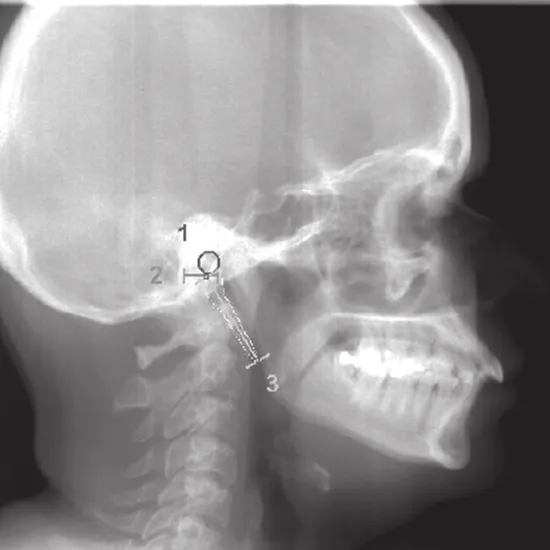

An X-ray of the styloid process is a non-invasive and painless examination that may reveal a pointed portion of bone that extends from the base of the skull to the area just behind the ear.

To identify abnormalities, deformities, aberrant growth, and broken/fractured styloid processes.

• To determine the presence of elongated styloid processes (Eagle's syndrome).

• To assess the calcification (extra calcium deposition) of the stylohyoid ligament that causes discomfort and inflammation in the neighboring area.